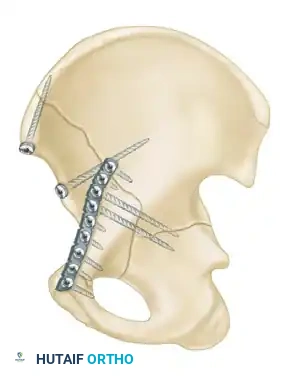

The Kocher-Langenbeck Approach

- Indications: Posterior wall, posterior column, and certain transverse fractures.

- Positioning: Prone or lateral decubitus. Prone positioning allows for easier reduction of the posterior column using gravity, while lateral positioning is preferred if the patient has severe pulmonary contusions or requires simultaneous access to the anterior column.

- Interval: The gluteus maximus is split in line with its fibers. The short external rotators (piriformis, obturator internus, gemelli) are tagged and released at their femoral insertions to expose the retroacetabular surface and the greater sciatic notch.

- Nerve Protection: The sciatic nerve must be identified and meticulously protected throughout the procedure. Keeping the hip extended and the knee flexed reduces tension on the nerve.